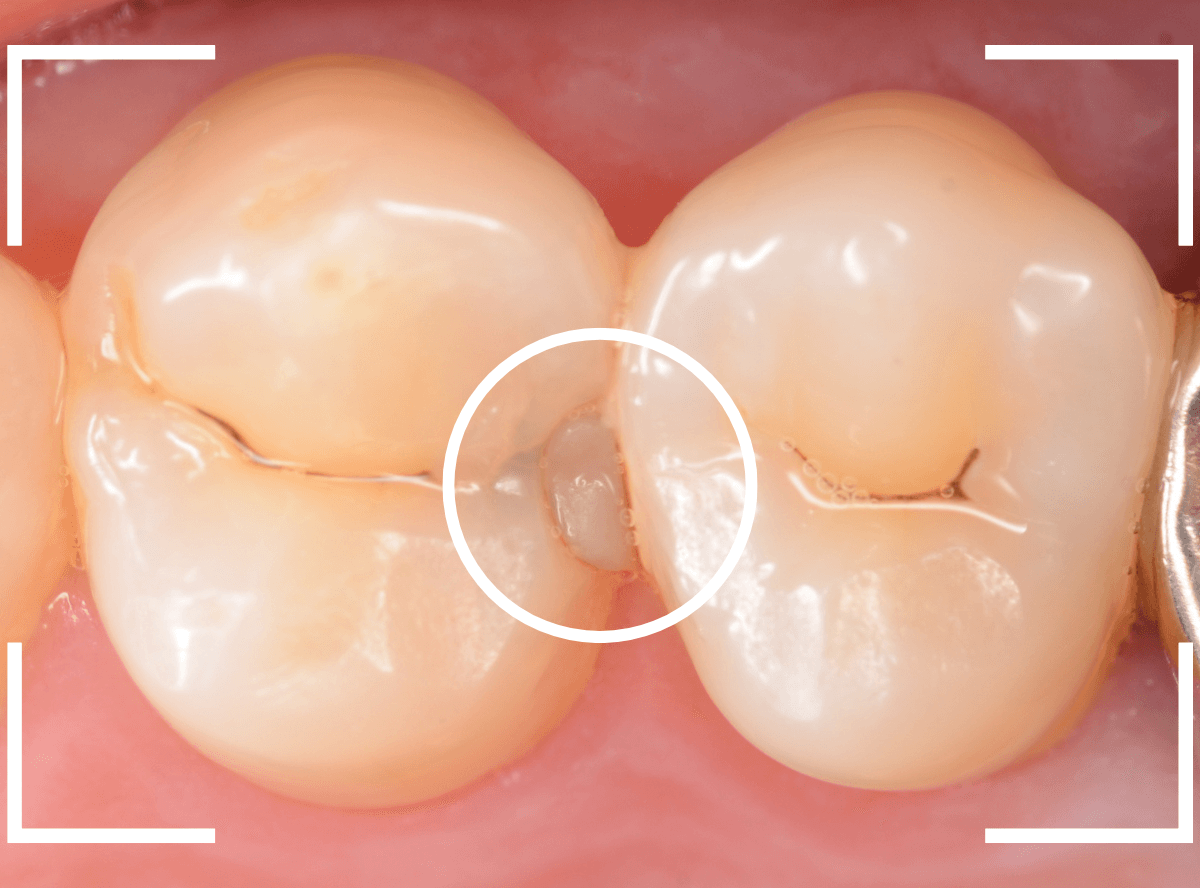

こちらは、下の奥歯の写真です。

特に症状の訴えはありませんでしたが、

歯を観察した瞬間、「虫歯がありそうだな」と思われるような所見です。

私の目には大体このように映っています。

レントゲン写真です。

私が虫歯っぽいと思っていた部分よりも、むしろ手前の部分に大きな虫歯がありました。

もう神経に触りそうな大きな虫歯です。

これだけの虫歯であれば、通常であれば、歯がしみたり、食事中に痛みがあったり何らかの症状があるのですが、無症状のこともあります。